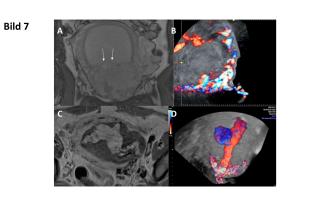

38-jährige 3102 mit St. n. Fetocid sowie MTX-Gabe bei Sectionarben-Schwangerschaft in der 14. SSW. Im Verlauf kommt es zur Geburt des Fetus, die Plazenta befindet sich jedoch noch in utero. Im MRI zeigt sich der V. a. eine Plazenta percreta mit möglicher Infiltration der Harnblase (Abb. 7A, Pfeil). Sonographisch kann dies nicht bestätigt werden. Die frühe Plazenta invadiert jedoch das Myometrium in Form einer Plazenta increta. In den Verlaufskontrollen lässt sich eine zunehmende Vaskularisation der Uterusvorderwand (Abb. 7B) nachweisen. Es wird der Entscheid zur Embolisation der Aa. uterinae links gefasst. Die Intervention muss bei Thoraxschmerzen vorzeitig abgebrochen werden. Die intrauterine Masse als auch die intramurale Durchblutung zeigen sich postinterventionell im MRI sowie sonographisch wenig reduziert (Abb. 7C und D). Bei anhaltend vaginalen Blutungen Entscheid zur LSC Hysterektomie, histologisch Plazenta accreta.